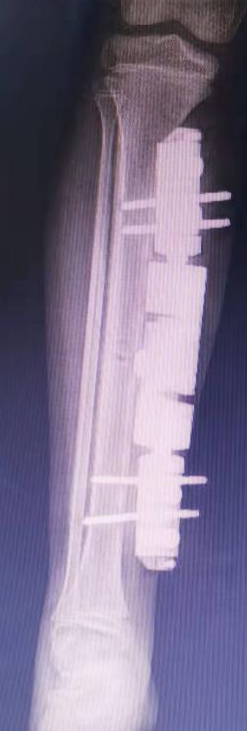

在创伤中心病房,赵刚主任精心组织了医护团队,紧张而忙碌的进行着各项准备,患者年龄较小,骨骼仍在生长,手术是否会影响患儿日后生长?患儿刚刚经历内脏出血,是否能够承受再次手术等?面临种种问题,创伤中心医护团队邀请相关科室会诊,为一切可能出现的情况做好准备,完善术前评估后,赵刚团队为患儿施行右股骨骨折切开复位内固定术+双侧胫骨骨折闭合复位外固定架固定术。术后给予抗炎、止痛等对症处理,现患儿恢复良好,已好转出院。

*术后骨折照片,可见骨折已得到复位及固定